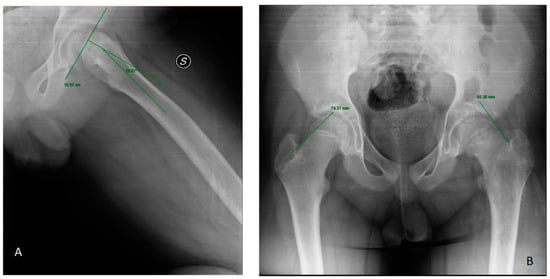

Billing et al. [] studied how the slipping angle (SA), according to the geometric method, was a more accurate diagnostic method than the conventional method (AP and FL view) (p < 0.05) in their case-control study. Three studies highlighted the diagnostic accuracy of the frog projection [,,], up to 100% sensitivity. “Trethowan sign” is evaluable in anteroposterior (AP) and frog-leg lateral (FL) view: the sign is positive when Klein’s line, a line extending along the superior femoral neck, does not intersect the physeal region []. In the FL view, the S-sign is a curved line drawn along the proximal femoral physis on the inferior border of the proximal femoral head-neck junction. Any breaks in the S-continuity, asymmetry or sharps turns were noted as abnormal tests that indicated SCFE []. Lastly, on the frog lateral hip view, Southwick slip angle is the most used measure of SCFE severity: it is defined as the angle formed by the shaft and a line perpendicular to the epiphysis [] (Figure 2).

Figure 2.

(A) Klein’s line. (B) Southwick slip angle in left SCFE.